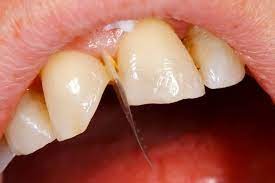

4 Longitudinal Fracture Issues And How They're Treated

Cracked teeth can happen due to a variety of circumstances: trauma due to an accident, chewing on hard food, a weak tooth structure. Sometimes, those cracks result in a type of damage called longitudinal fractures. While these fractures don’t always cause symptoms, they can cause pain and grow bacteria, which can lead to irritation and infection. Luckily, dental professionals can treat longitudinal tooth fractures, and the process to recovery will depend on the type of fracture. Here are the four types to be aware of.

Types of Longitudinal Fractures

1. Craze lines: While craze lines are considered a fracture, they’re not considered a dental emergency and generally do not need treatment. That’s because these lines only affect the tooth enamel and do not cause pain. Teeth grinding, nail-biting, or changing temperatures in the mouth may cause these types of fractures. While these cracks should not cause concern, some adults seek out cosmetic fixes like teeth whitening.

2. Fractured Cusp: Fractured cusps occur when a piece of a tooth’s chewing surface breaks off, typically near a filling. This type of fracture usually does affect your pulp or cause pain and typically can be repaired through a filling or crown.

According to a report in the Journal of Clinical & Diagnostic Research, fractured cusps are the most common type of longitudinal fracture. A number of conditions may cause them:

Teeth weakened by restorations

Large cavities

Age

Traumatic injuries

Abnormal biting habits, such as teeth grinding

If you do have a fractured cusp and experience pain or sensitivity to cold fluids, reach out to your dental professional for immediate attention.

3. Cracked Tooth: A cracked tooth is when a crack extends from the crown of the tooth toward the root, though the tooth is not split into pieces. This fracture is more extensive than a fractured cusp and, therefore, more likely to affect the nerve of the tooth. There are several possible causes for a cracked tooth, including:

Teeth grinding

Dental work that weakened the tooth

Trauma to the tooth

Treatment will vary based on the location and extent of the crack, which your dentist may need to investigate. If the nerve of the tooth is affected, an endodontist might perform a root canal treatment. If the crack extends down below the gumline, the tooth may need to be extracted.

4. Split Tooth: A split tooth is a complete fracture from the crown that extends below the gumline through the middle of the tooth. This is usually the result of an untreated cracked tooth, as the fracture extends over time, it can happen either suddenly or due to the long-term growth of the crack. The tooth may require extraction, but in some cases, an endodontist may save a portion of the tooth and complete a restoration to make the tooth functional.